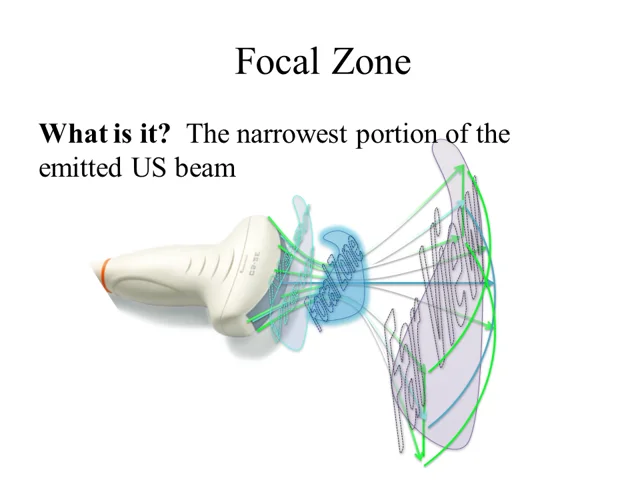

What is the focal zone?

The region of the image at which the ultrasound beam is the narrowest (where lateral resolution is the best).

Where should the focal zone be set at?

Slightly behind what you are looking at.